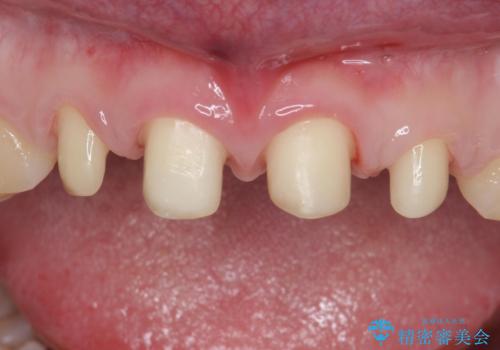

- 右上12左上12 : 仮歯 / 11,000円×4本、ジルコニアクラウン(スペシャル) / 154,000円×4本 合計660,000円(税込)費用は治療当時の料金となります

形のイメージを反映させた仮歯を調整し、技工士さんと連携して製作したため口元に調和した非常に審美的なクラウンを装着することができました。